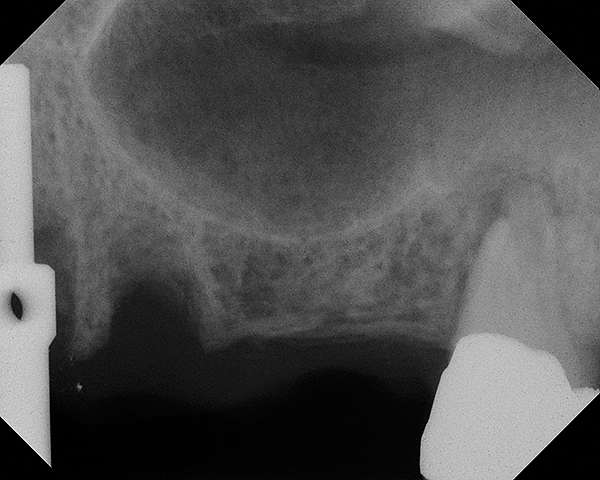

This patient was a 73-year-old man with only about 3.5 mm of native bone in the No. 3 site (Figure 20). The composite graft used here was a 50:50 mixture of DFDBA and deproteinized bovine bone mineral (Osteohealth, www.osteohealth.com) with approximately 40% calcium sulfate added. The implant was the same type and length as in Case 1 above. Figure 21 shows the area on the day of placement. In the CBCT scan on the day of placement (Figure 22), the native bone and bone graft were clearly discernable. However, the postoperative radiograph taken at 6.5 months (Figure 23) showed no marginal bone loss and a significantly denser appearance than when the graft was place. The membrane was raised about 7 mm to 8 mm. The final radiograph was taken after extraction of tooth No. 2 and after extraction of tooth No. 4 and immediate implant placement.

Fig 16. 4-month radiograph with the abutment No. 14 in place. Note the ill-defined old sinus floor.

figure 16